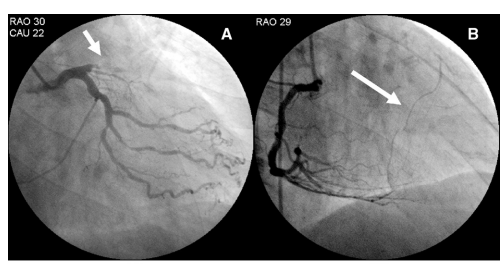

What is the lesion?

It looks like an  Intracardiac tumor, a myxoma ? a variant of HCM ?  Is it a hydatid cyst, ?

No it’s not. I can give one clue. This is a man-made condition.

Oh ok, did this happen inside the cath lab ?

Yes, you got it, right. But need a diagnosis.

Can you give me one more clue?

This patient was undergoing PCI for chronic total occlusion.

So, it must be a complication. Then I need to know the list of complications during CTO PCI.

Yes, but you may not find this one in the conventional list. Let me come out with the answer.

Answer

It is a huge septal hematoma due rupture of vulnerable septal collateral during retrograde wiring for opening LAD CTO.It usually occurs due to o prolonged procedures and hardware-related injury. Thanks to the authors from Taiwan to post this case report. (Image Courtesy Lin & Wu 2005 Ref 1)

Lessons from this case report (Not meant to offend anyone )

This case gives us some important lessons to be learned. One of my senior colleagues used to say, opening a CTO is ok, but using a retrograde approach with aggressive deploying of hardware within the last remaining lifeline provided by the donor coronary artery is a culpable coronary crime unless it is a life-saving procedure.

The often used term “septal surfing” adds an “adventure sport feel” to our youngsters posing as an interventional challenge and amplifying the potential injury. The fact that epicardial collaterals have a larger caliber, but the temptation to cross it, is significantly suppressed (or even forbidden) due to the risk of tamponade. However, this doesn’t in any way give us the freedom to toy with septal collaterals. Proliferating hardware  (Innovative though ) is also an issue. It is true, technological input is a pillar for the growth of science. However, it is a sad fact, many of us are compelled to learn risky, unscrutinized tricks exclusively from academically unbaked industry guys, rather than from mainstream literature.

Final message

“No procedure … no complication”

I could recall, one of my colleagues displayed this caption as the last slide in a cath lab workshop,  after a talk on How to avoid complications in the cath lab.

Very true. But, CTO by itself never belongs to a malignant subset of CAD, as some sections of the cardiology community would want us to believe. CTOs do need an intervention, only as a  life-saving /0r severe symptom-relieving procedure. Most of them aren’t.  They present with stable angina because of extensive collaterals.  Unfortunately, instead of respecting this, many of us are asked to close these channels and try to maintain antegrade flow. The irony is, to open the CTO we may end up sacrificing these life-saving channels.

Reference

1.Lin, T.-H., Wu, D.-K., Su, H.-M., Chu, C.-S., Voon, W.-C., Lai, W.-T., & Sheu, S.-H. (2006). Septum hematoma: A complication of retrograde wiring in chronic total occlusion. International Journal of Cardiology, 113(2), E64–E66. doi:10.1016/j.ijcard.2006.04.032